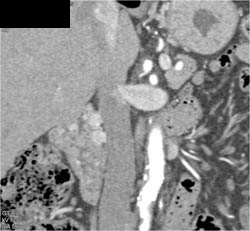

Perforated Gastric Mass